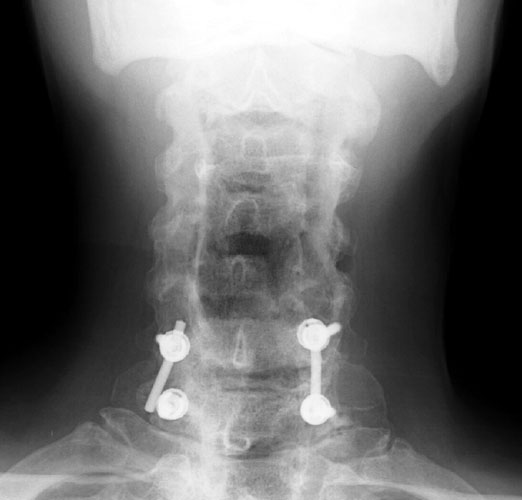

Slipped Rod

3 months later,

follow-up films show the posterior fixation at C6-7. Now noted that the

screw at C7 has slipped off the support rod on the right. |